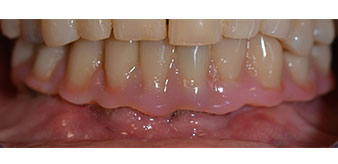

Die 64-jährige Patientin wurde mit einer Unterkiefer-Restbezahnung 38, 33 und 43 und einer klammerbefestigten Interimsprothese im Unterkiefer vorstellig (Abb. 1 und 2).

Im Anschluss erfolgt die Abformung und Bissnahme, sodass die Zahntechniker umgehend mit der Anfertigung der provisorischen Arbeit beginnen können. Diese wird im Anschluss am gleichen Tag eingeschraubt (Abb. 17 und 18).

Nach der Zeit, die für die Osseointegration benötigt wird, kann die endgültige Abformung der Implantate erfolgen und entsprechend die endgültige Arbeit angefertigt werden (Abb. 19 und 20). Hier können Behandler und Patient gemeinsam entscheiden, ob diese eine Keramik- oder Kunststoffverblendung, ein Zirkon- oder Metallgerüst bekommen soll. Im vorliegenden Fall hat sich das Team um Dr. Pascu, aufgrund der unklaren Prognose der Oberkieferbezahnung und des elongierten Zahnes 24, für eine Kunststoffverblendung entschieden. Diese ist im Allgemeinen wesentlich einfacher umzustellen und der neuen Situation im Oberkiefer anzupassen.